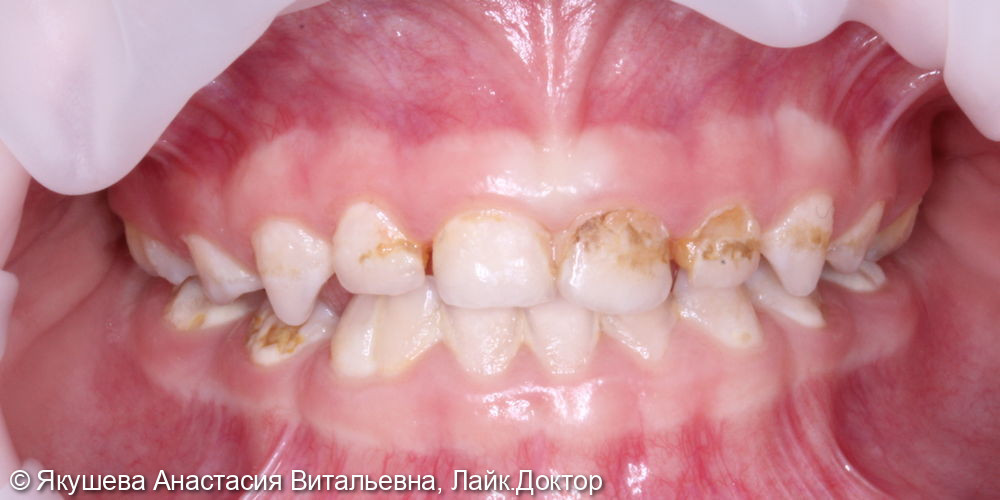

55;54;64;85;84;74;75 : К04.0 Пульпит (K04.0 Пульпит)

53;51 - 63;65;83;73 : К02.1 Кариес дентина (K02.1 Кариес дентина)

55;54;64;85;84;74;75 : в условиях общего обезболивания: очищение мягкого зубного налета, изоляция коффердам, проведено препарирование кариозной полости, раскрытие полости зуба, проведена пульпотомия, достигнут гемостаз,Показать полностью...

55;53;65;74 : в условиях общего обезболивания очищение мягкого зубного налета, изоляция коффердам, проведено препарирование кариозной (ых) полости (ей), под контролем витального окрашивания «Кариес Маркер» удалены деминерализованные участки эмали и дентина, формирование кариозной полости антисептическая обработка раствором хлоргексидина 2%,Показать полностью...